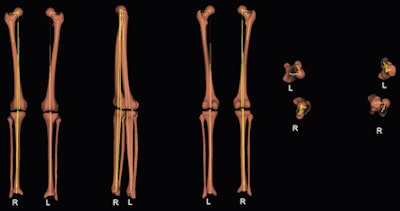

The group took 3D measurements of eight dried bones, analyzing them with the EOS system using stereoscopic software and comparing the measurements with 3D CT. Also, 47 lower limbs of children and adolescents were studied using biplanar low-dose x-ray 2D and 3D measurements. Both parts of the study were evaluated for femoral length, tibial length, femoral mechanical angle, tibial mechanical angle, frontal and lateral knee angulations, and the femoral neck-shaft angle.

Above: From left to right, the calibration points, the contours, and the 3D measurements. Below: From left to right, 3D reconstructions views: frontal, lateral, back, up, and down. All images courtesy of Dr. Ramon Gheno.

The researchers found the 3D comparison between the EOS system and CT showed no significant differences in femoral length, tibial length, femoral mechanical angle, tibial mechanical angle, frontal knee angulation, lateral knee angulation, and femoral neck-shaft angle.